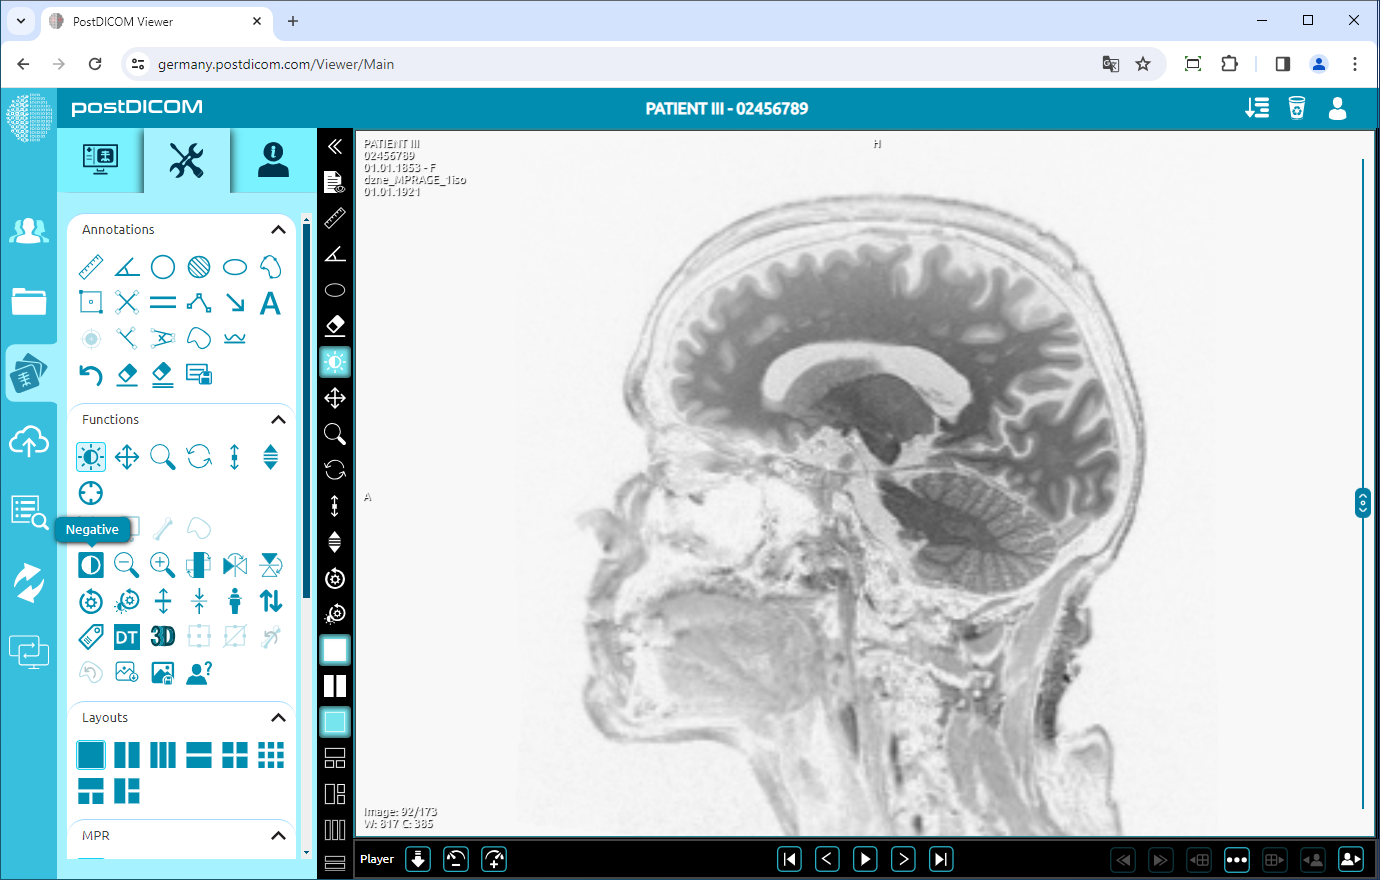

Negate

To negate the image, click on the “Negative” icon on the left side of the page.

After clicking, you will see the inverted image on the viewport. If you want to see normal image click again.